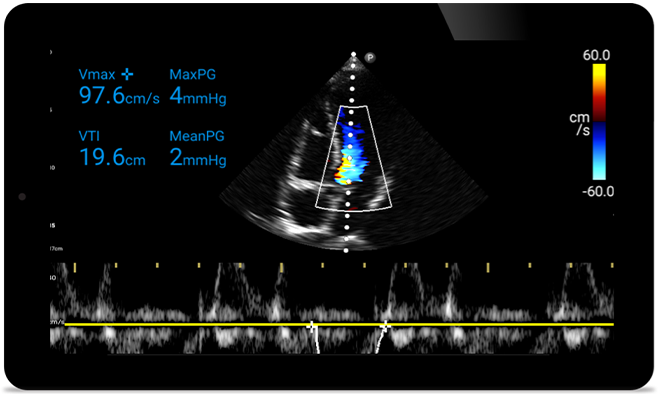

Act faster to protect their heart

Act faster to protect

their heart

When seconds count, portable ultrasound can make the difference. Lumify can provide the high-definition imagery you need whenever and wherever you need it.

Broadband phased array transducer

Lumify S4-1 broadband phased array transducer

• 4 to1 MHz extended operating frequency range.

• 2D, Color Doppler, M-mode, advanced, XRES and multivariate harmonic imaging.

• High-resolution imaging for abdominal and cardiac applications: cardiac, OB/GYN, lung, abdomen and FAST imaging preset optimizations.